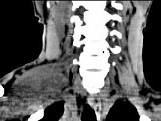

问题 女,47岁,下颈部触及一包块约5年余,CT如图所示,最可能诊断为()

选项 A.滑膜肉瘤 B.血管瘤 C.神经鞘瘤 D.副神经节瘤 E.巨淋巴结增生症

答案 C